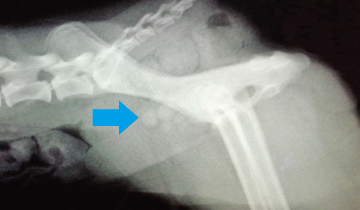

血尿を主訴に来院したプードルです。レントゲン検査と超音波検査で膀胱結石と診断しました。

矢印で示したのが結石です。